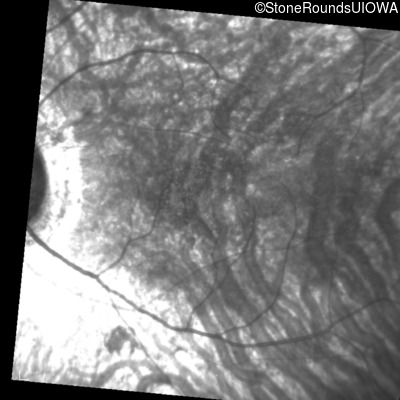

Infrared Fundus Photograph - Left - 20/100 sc

Exemplar